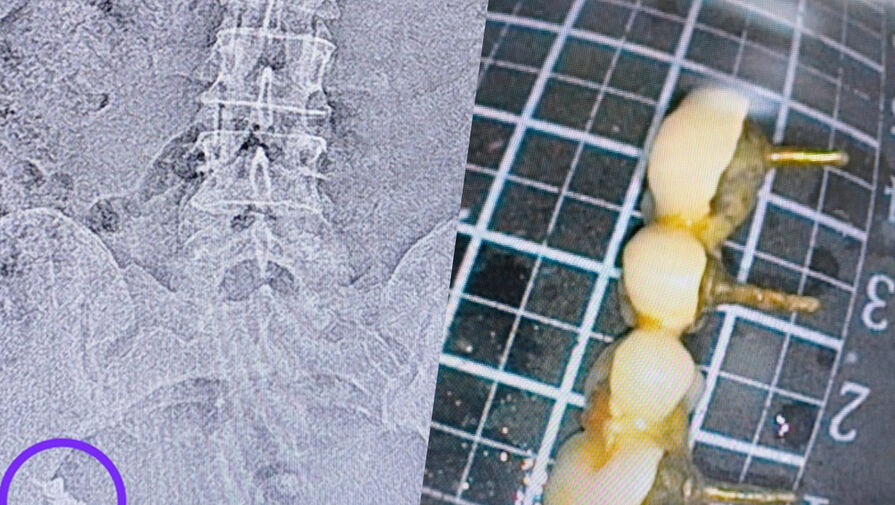

Врачи Республиканской клинической больницы в Казани помогли 50-летней женщине, которая проглотила зубной протез. Об этом сообщили в пресс-службе медицинского учреждения.

По словам медиков, от извлечения устройства с помощью эндоскопа пациентка неоднократно отказывалась, как и от госпитализации, надеясь на то, что протез выйдет сам.

В итоге прогноз пациентки не оправдался, через неделю ее госпитализировали в хирургическое отделение больницы. Обследование показало, что протез застрял в области перехода тонкой кишки в толстую.

«Врач-эндоскопист Наиль Зуфарович Исхаков во время колоноскопии удалил протез. Процедуру делали под контролем анестезиолога-реаниматолога Елены Александровны Чуенковой, так как протез находился уже в труднодоступном месте. С анестезией процесс удаления прошел безболезненно для пациента», — рассказали в пресс-службе больницы.